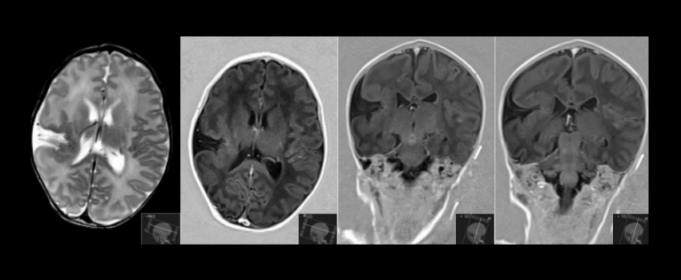

Schizencefalia - afecțiune neurologica determinată de o dezvoltare anormală a creierului ce apare între prima și a șaptea lună de gestație. Simptome: microcefalie, macrocranie cu hidrocefalie, paralizii ale membrelor, întârziere în dezvoltarea psihică, convulsii, care în 80% din cazuri apar sub vârsta de 3 ani.